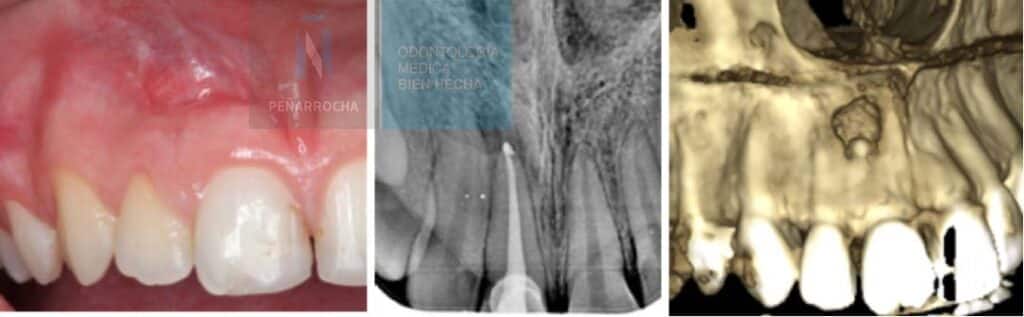

Endodoncia mal hecha: síntomas, causas y qué puedes hacer

¿Te han hecho una endodoncia y notas que algo no va bien? Este tratamiento se realiza con el fin de evitar la pérdida de un diente con caries que está muy dañado. Aunque cada vez se realizan mejores endodoncias y técnicamente están bien hechas, se calcula que el fracaso de una endodoncia oscila entre el 2 […]